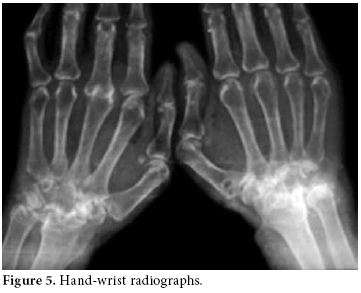

The RA disease activity score (DAS) was calculated as 6.14. Predominant findings in hand X-rays were symmetric joint erosions in carpal bones along with ankylosis leading to contracture, joint space narrowing, cystic changes, and periarticular osteoporosis (figure 5).

In foot-ankle X-rays, periarticular osteoporosis, hallux valgus, and joint space narrowing had progressed to the ankylosis of tarsal bones (figure 6).